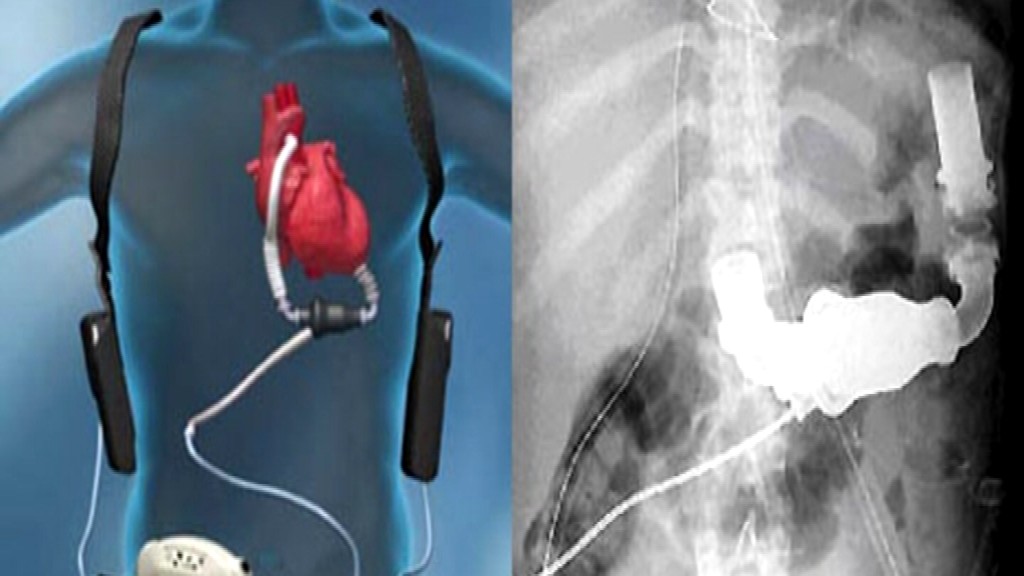

160 tisíc eur. Presne toľko stojí umelé srdce, ktoré aj na Slovensku už zachránilo život 17 ľuďom. Nejde však o žiadne sci-fi robotické srdce, ale jednoduchú pumpu, ktorá nahrádza zlyhávaciu srdcovú komoru a namiesto nej pumpuje krv do organizmu...

Funguje na princípe mechanického čerpadla. V magnetickom poli sa otáča magnetická vrtuľka. Tá čerpá krv z komory do organizmu a tým nahrádza funkciu poškodenej komory. Pán Motyčka má jedinú starosť - vymieňať si približne každé štyri hodiny baterky.

Pumpa môže byť v tele zavedená až 5 rokov. Najdlhšie ju mal pacient asi 500 dní. Pacienti s pumpou sú totiž čakateľmi na transplantáciu. "Sú vyradení z toho akútneho zoznamu a dávaní na normálny čakací zoznam," informoval Michal Hulman, primátor oddelenia srdcovej chirurgie NÚSCH. Pánovi Motyčkovi vložili pumpu do hrude koncom roka 2009. Dnes má už za sebou úspešnú transplantáciu...